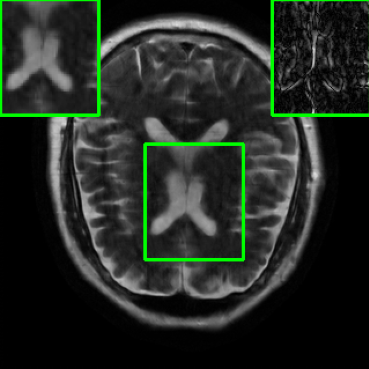

Performance on Data with Lesions: While the previous experiment allowed comparing reconstruction quality with or without planted features, here we test our method on MRI scans with lesions, which are often regions of abnormal or diseased tissue. We utilize the annotated fastMRI+ data666https://github.com/microsoft/fastmri-plus/tree/main to evaluate our method’s image reconstruction capabilities, and compare its outcomes with established baselines. For the training phase, the non-lesion dataset was employed for the global training approach with images whereas LONDN-MRI used adaptively selected images for training (searched from images). In contrast, during the testing phase, we used scans with lesions. The results, as displayed in Table V, indicate that our method achieves substantially higher PSNR values in comparison to the globally trained baseline as well as the LORAKI method. Furthermore, visualizations in Figure 16 clearly demonstrate the superiority of our method, particularly in the nonspecific white matter lesion areas. Thus, both in terms of visual assessment and PSNR values, our approach outperforms the existing baselines and aligns more closely with the ground truth.

| Ground Truth | LORAKI | Global | LONDN-MRI | LONDN-MRI | Oracle |

| (1 iteration) | (2 iterations) | ||||

![]() |

| PSNR = dB | PSNR = 33.17 dB | PSNR = 35.10 dB | PSNR = 35.67 dB | PSNR = 35.74 dB | PSNR = 35.87 dB |